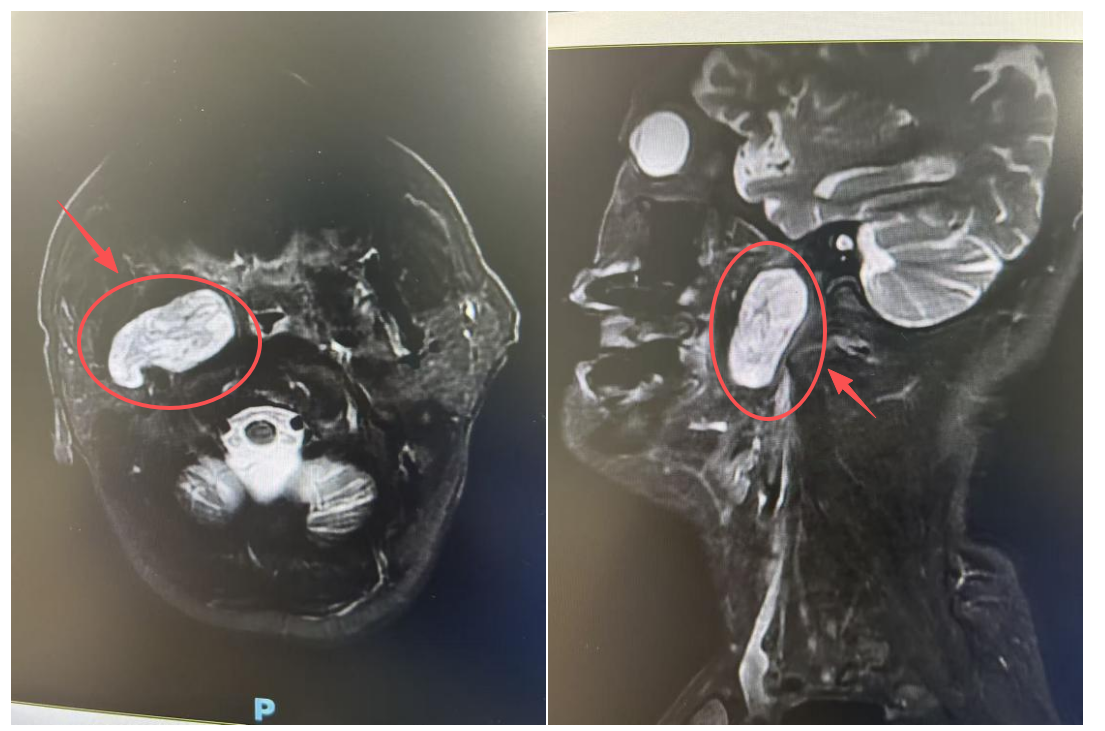

两年前,王爷爷在检查中发现自己的咽旁间隙长了一个肿瘤。虽然医生评估可能为良性,但近期复查显示肿瘤范围有所增大,已经达到5×2.5×5cm,相当于一个鸡蛋这么大。这让王爷爷和家人忧心忡忡——肿瘤继续增长,可能压迫周围重要的神经和血管,影响吞咽及呼吸功能,甚至带来更多的风险。这就像一把利剑,时时刻刻悬在头顶上。

经过南医大二附院耳鼻咽喉科程友主任团队的详细评估,王爷爷的肿瘤范围较大,位置较深。可用的手术方案有两种:

从口腔内部操作,体表无切口。但咽旁间隙位置较深,含颈内动脉、静脉,迷走神经、舌咽神经等重要血管神经,有发生大出血、神经损伤等严重并发症风险。同时,内镜手术空间狭窄,医生需要在有限的空间完成肿瘤切除,手术难度高,对医生的考验大。

考虑到王爷爷的身体状况和对术后生活质量的高要求,程友主任团队经过反复论证,决定选择第二种更具挑战性的“经口入路”方案。该方案虽然对医生的手术技术要求高,但一旦成功,患者将获得创伤更小、恢复更快、且面部不留疤痕的显著优势。